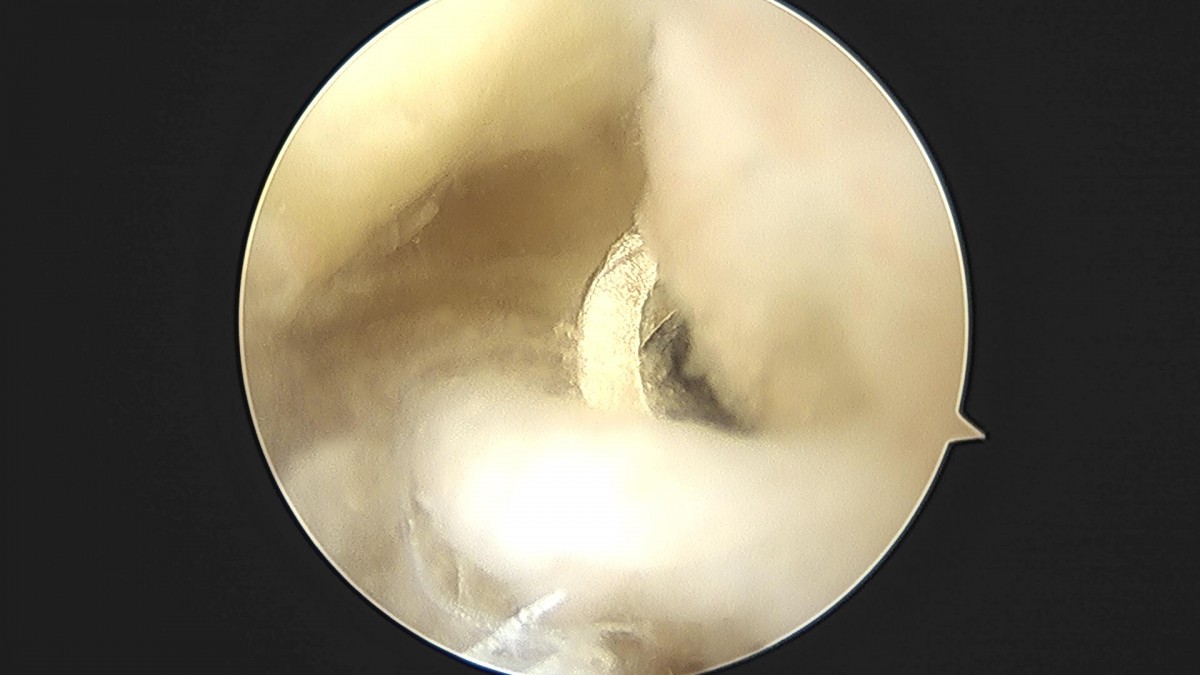

이재상원장님 무릎 반월상연골판 절제술 홍성O 환자

작성자 최고관리자 댓글 0건 조회 2,216회 작성일 23-01-12 17:54